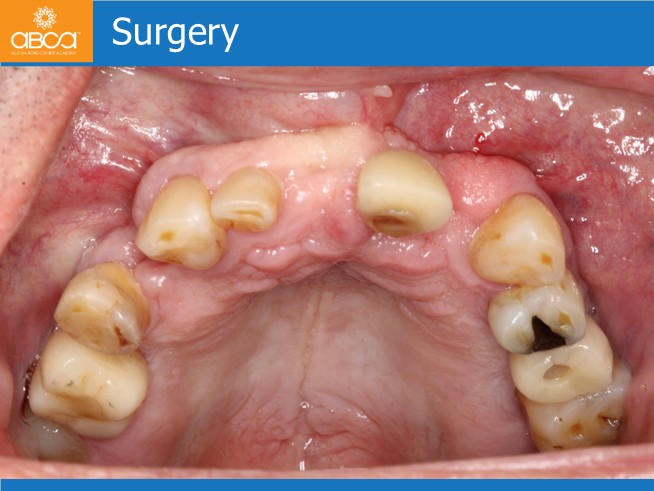

Treatment includes the extraction of all the remaining teeth, careful cleaning of all the sockets. Without opening a flap, placement of 3 implants to achieve an All-on-6, socket grafting and immediate load. Placement of the final Nobel Procera hybrid prothesis after 6 months.